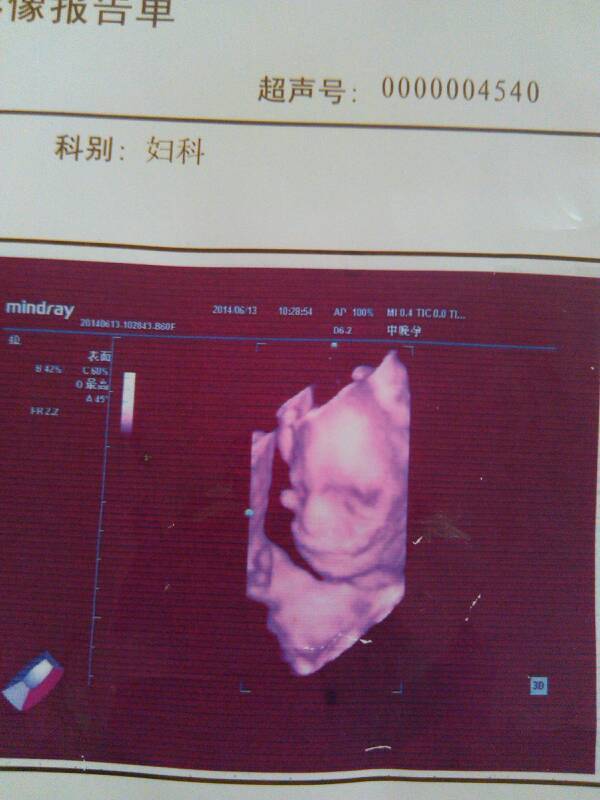

4月23号检查14周+6为什么到了6月13号晕周才整20周,下面是B超单子 4月23号检查14周+6为什么到了6月13号晕周才整20周,下面是B超单子 点击展开 泠汐 2014-06-29 13:12 为您推荐: 其他回答 不同的检查时间,判断是可能有误差的,误差不多是没事的,这个是很常见的,不必担心. 可爱的笑娟 2014-06-29 19:07 相关问题 我20周的时候坐b超,单子上显示21~22周? 我整8周的时候去照b超,单子上胎囊大小是54mmx48mmx27mm,大夫说八周这数据有点大,也没